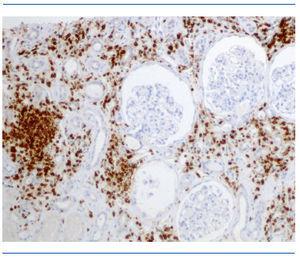

Dadas las características de la clínica, y sospechando un síndrome ojo-riñón, se realizó una biopsia renal. En la microscopia óptica se observaron glomérulos bastante conservados, no se hallaron depósitos fucsinófilos con el método de tinción tricrómico de Masson (figura 2), ni se detectaron alteraciones de la membrana basal de los capilares glomerulares; el estudio con plata-metenamina mostró cambios discretos-moderados en el intersticio junto con infiltrados de mononucleares con células plasmáticas y linfocitos T (CD3) (figura 3). Los túbulos renales mostraban la destrucción de alguno de ellos con reacción mesenquimática hacia su componente hialino luminal y otros mostraban ligera dilatación de la luz con alteraciones en su revestimiento epitelial y la luz ocupada por un material proteináceo con restos celulares. También se objetivaron hallazgos de fibrosis intersticial y atrofia tubular. El resto del estudio inmunohistoquímico con inmunofluorescencia y aplicación de antisueros fue negativo. Se diagnosticó una nefritis túbulo-intersticial con predominio de infiltrados intersticiales de linfocitos T (figura 3).

Figura 3. Biopsia renal. Plata-metenamina: infiltrados de mononucleares con células plasmáticas y linfocitos T (CD3).